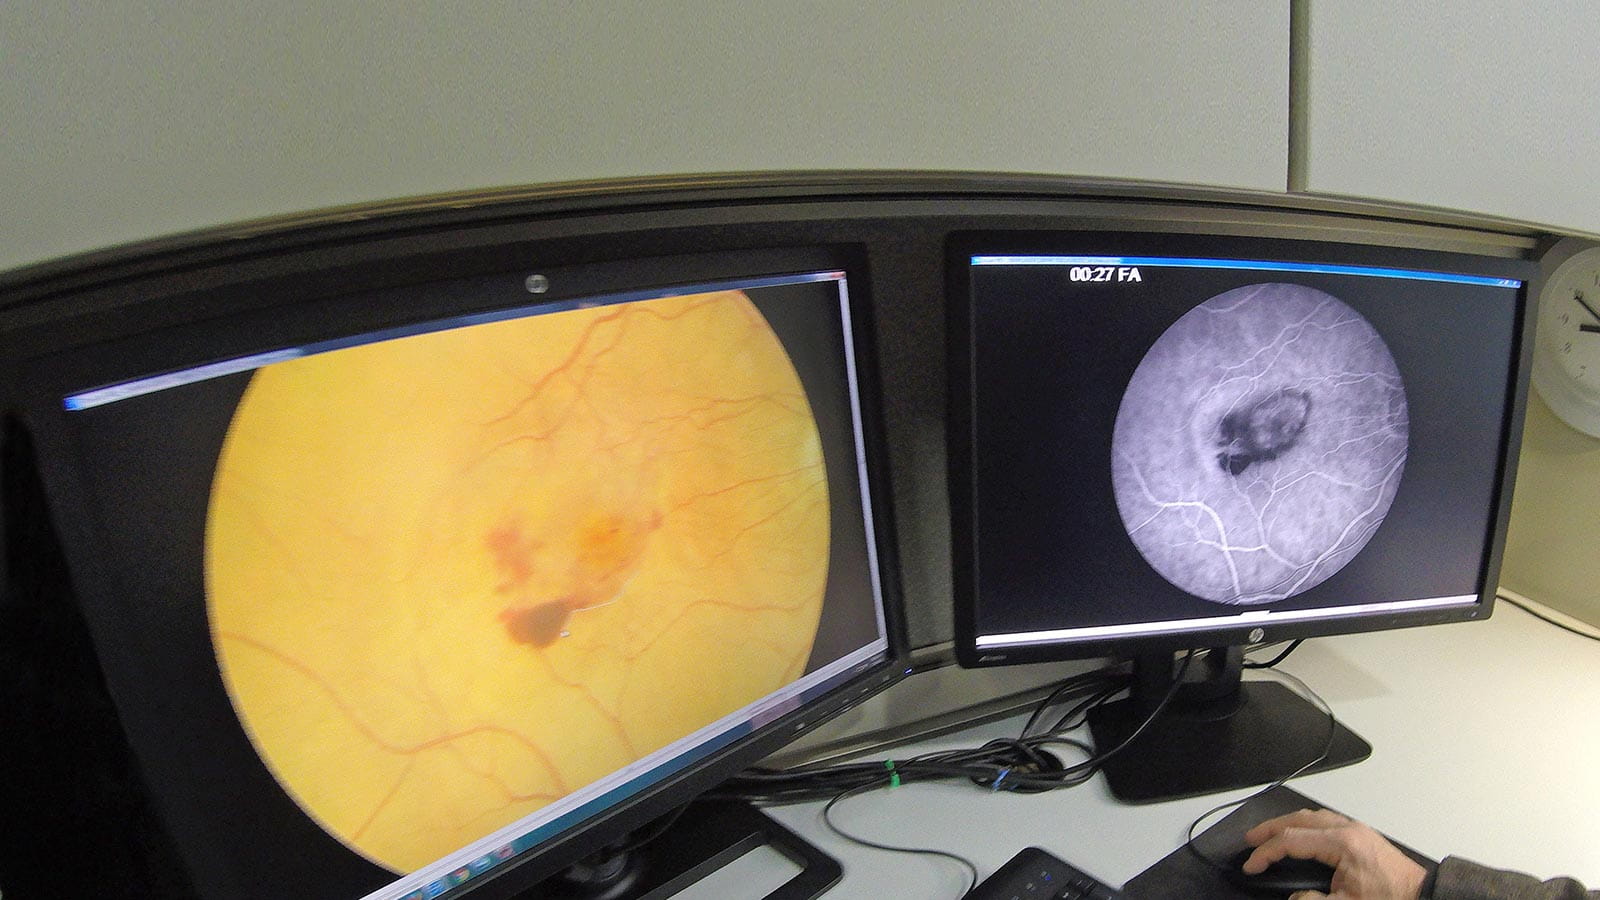

Retina Diseases Imaging Analysis Reading Center

Evaluates the pathology of fundus photographs, fluorescein angiograms, or other retinal imaging modalities for prospective clinical trials.

We evaluate images assessing efficacy and safety related to drugs and for a variety of retina-vitreous disorders such as diabetes, neovascular and non-neovascular macular degeneration, uveitis and retinal detachment.